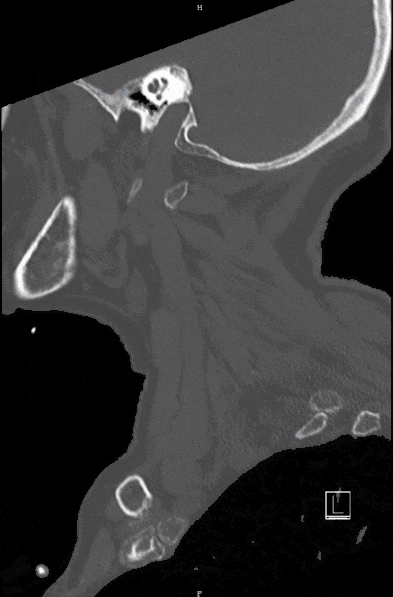

Spinal column injuries can not only lead to fractures, thus instability, but thereby threaten the spinal cord and nerves in particular. The spinal cord syndrome is one of the most severe injuries and can lead to paralysis, sensory disturbances as well as bladder and rectal emptying disorders and even respiratory disturbances.